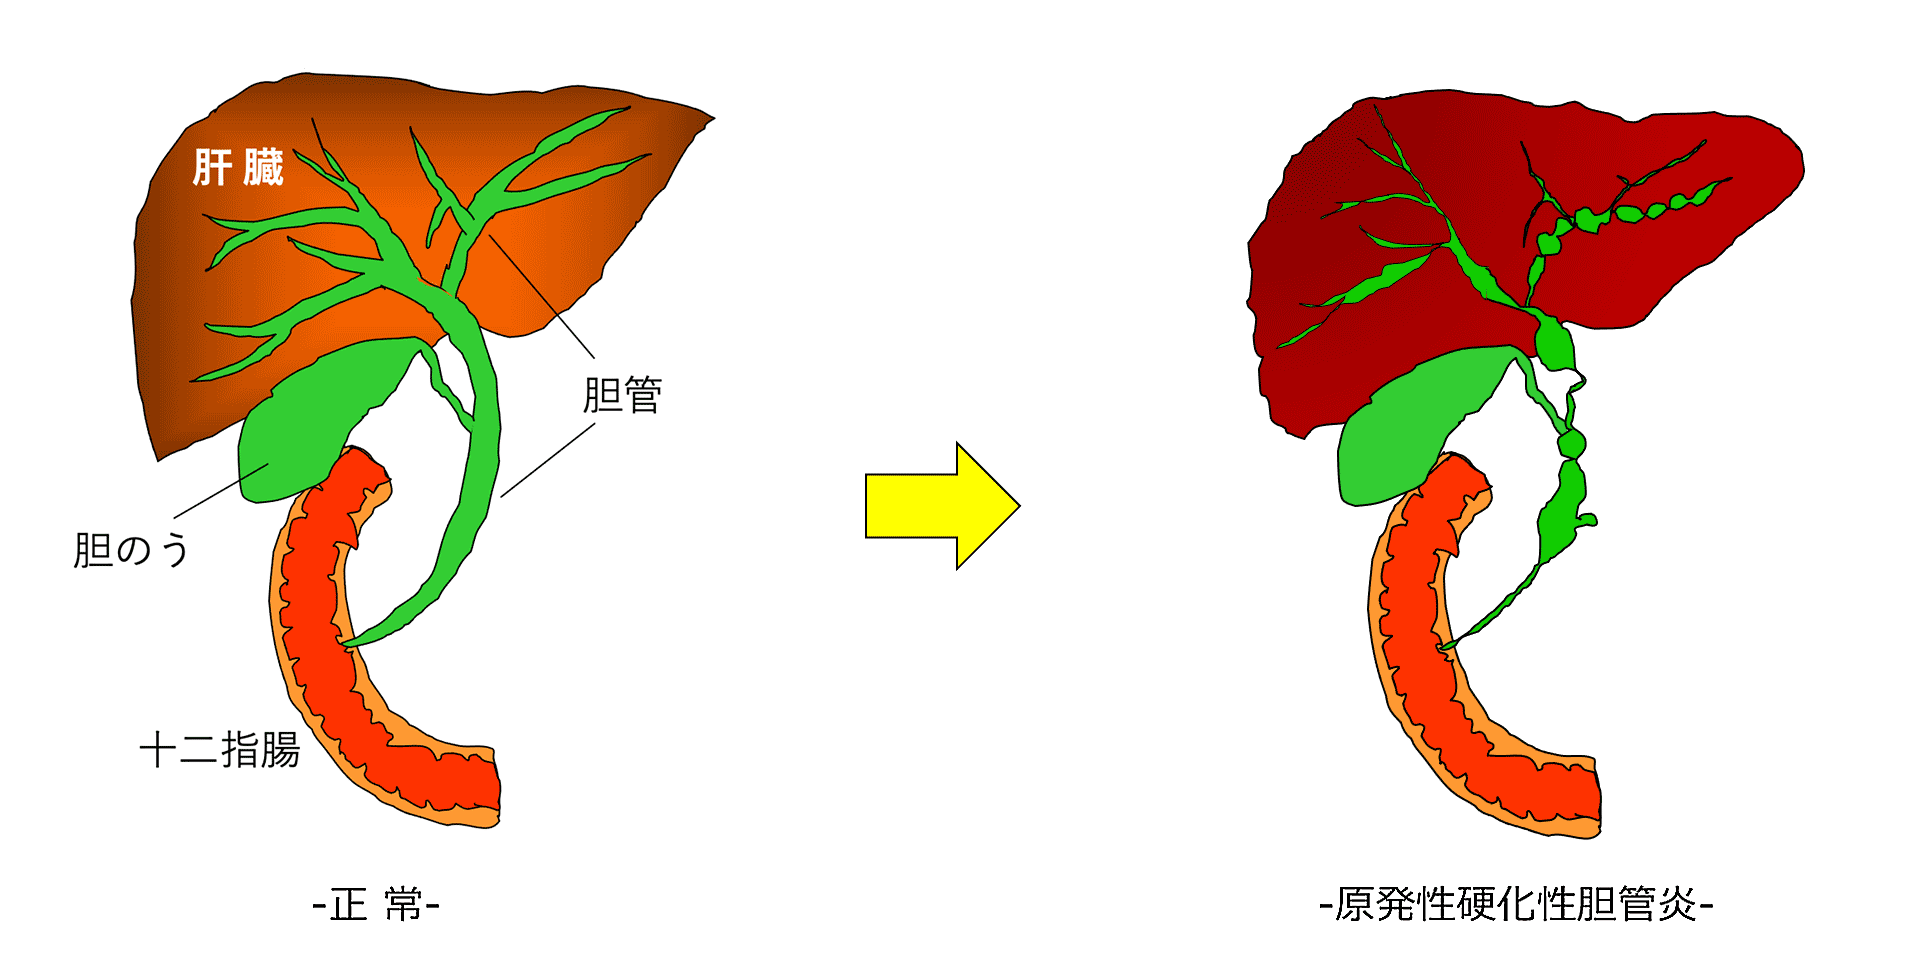

以前は原発性胆汁性肝硬変として知られていた原発性胆汁性胆管炎 (PBC) と原発性硬化性胆管炎 (PSC) はどちらも胆管の破壊を伴います。どちらの症状も自己免疫反応が原因であると考えられています。

胆管は胆汁を肝臓から胆嚢および小腸に運びます。胆汁は、食べ物に含まれる脂肪を体が分解するのを助けます。

PBC と PSC は両方とも胆管の損傷を伴います。 PSC は主に肝臓の内外の中・大胆管に損傷を引き起こします。 PBC は、肝臓内の小さな胆管の損傷を特徴としています。